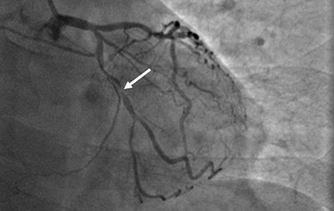

近日,河北醫(yī)科大學(xué)附屬燕達(dá)醫(yī)院心血管內(nèi)三科成功完成一例非常特殊的手術(shù)——冠心病三支病變微創(chuàng)介入完全血運重建術(shù)。患者李先生冠心病病變極其嚴(yán)重,全部三支主干動脈均重度狹窄,各處求診均被告知無法微創(chuàng)介入手術(shù),只能開胸搭橋。拒絕開胸的李先生慕燕達(dá)醫(yī)院心血管內(nèi)三科北京安貞醫(yī)院專家團(tuán)隊之名,就診于燕達(dá)醫(yī)院,由翟光耀主任為其行 “一站式”手術(shù),一 次 性完成三支動脈的修復(fù)!手術(shù)非常成功,李先生術(shù)后恢復(fù)良好,滿意出院。   震驚 患者三支血管均90-99%狹窄 ..